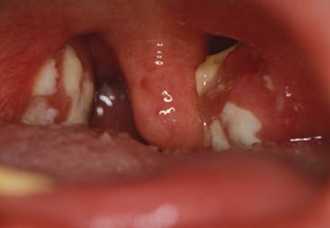

- Осмотра глотки. При фарингоскопии на верхней трети или всей поверхности одной из небных миндалин визуализируется серовато-желтый или зеленый налет по типу пятна от стеариновой свечи. Изредка он выявляется на передней небной дужке. После снятия мембраны пуговчатым зондом обнаруживается кровоточащая поверхность желтоватого цвета с четкими границами, покрытая язвами и участками некроза,

Общая симптоматика не выражена или выражена слабо. Обычно поражается одна миндалина. На ее поверхности образуются поверхностные язвы, покрытые серо-зеленым налетом с гнилостным запахом. При удалении налета миндалина кровоточит. После отторжения некротизированного участка образуется глубокая язва, которая в последующем заживает без образования дефекта.

- При некротической ангиневиден плотный серый или зеленовато-желтый налет с неровной, тусклой, изрытой поверхностью. При удалении налета ткань миндалины кровоточит. После отторжения участков некроза остаются дефекты ткани неправильной формы диаметром 1-2 см. Возможно распространение некроза за пределы миндалины на заднюю стенку глотки, язычок и дужки.

- налет на миндалине имеет желтовато-серый цвет, зачастую с зеленым оттенком;

- налет рыхлый, легко сдвигается, обнажая кровоточащие язвы с неровным краем;

Какие симптомы указывают на то, что у человека развивается язвенно пленчатая ангина? Во-первых, данная болезнь может иметь 2 формы – язвенную и ложнопленчатую (что отражается в ее названии). При ложнопленчатой форме на поверхности миндалины появляется налет в виде пленки, напоминающий поражение горла при дифтерии. По этой причине пленчатый тонзиллит иногда также называют дифтероидным. При язвенной формепоражение миндалины имеет вид язвы, покрытой рыхлым грязно-белым налетом.

- язвы на поверхности пораженной миндалины округлые, с серым дном и ровным краем;

- язвы покрыты налетом грязно-белого или желтоватого цвета, рыхлой консистенции (при дифтероидной форме налет выглядит плотным, пленкообразным, но легко снимается при касании ватным тампоном);